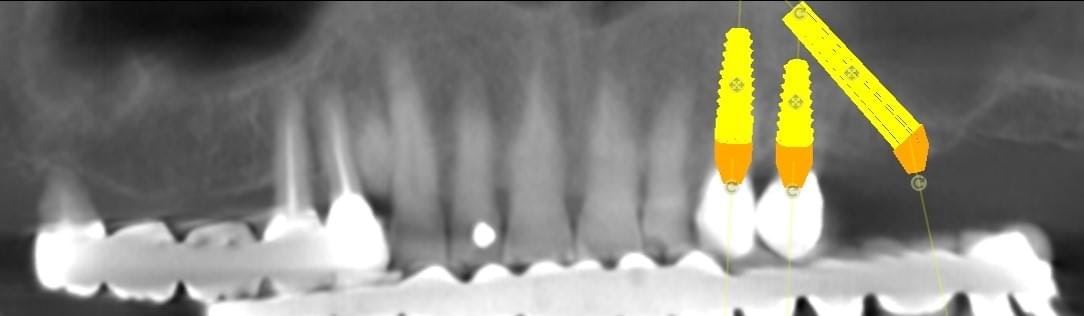

For moderate to severe maxillary atrophy, in the presence of surgically challenging sinus anatomy, the apex of the posterior implants can be angled anteriorly, passing transsinus, to apically fix at the lateral piriform rim into the lateral nasal wall. The most important bone for apical fixation of implants in this setting is the lateral nasal bone mass with the maximum available bone found at the piriform rim above the nasal fossa (4,5). This area, designated the M point, also can engage two implants placed at 30-degree angles (Figs. 1a-b). The transsinus implants are then grafted and possibly placed into immediate function, depending on the level of crestal stability present.

Digital implant project: three different views of the same procedures.